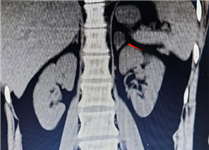

对于肾上腺腺瘤的诊断,需要综合运用多种检查手段。实验室检查如激素水平测定,有助于判断肿瘤是否具有功能性以及分泌的激素类型。影像学检查,如CT、MRI等,能够清晰地显示肿瘤的位置、大小、形态等特征,为诊断和治疗提供重要根据。

如果体检发现肾上腺腺瘤,首先要明确它是否“有功能”:通过CT或MRI明确腺瘤的大小、位置、形态,帮助判断性质。

肾上腺CT正常表现

1.形态:形态各异;右侧:斜线状、倒“V”、倒“Y”形;左侧: 倒“V”、倒“Y”形或三角形;三维重建呈叶状。

2.大小: 侧支厚度<10mm;侧支厚小于同侧膈肌脚,面积小于150mm。

3.密度: 均匀,边缘光滑,无外凸结节。

4.强化: 均匀,边缘光滑。

肾上腺腺瘤CT表现

1.肾上腺腺瘤发生于肾上腺皮质,含脂质;

2.直径多小于3cm;

3.CT值<10HU;

4.出血、坏死、囊变少见;5.CT增强:早期快速廓清